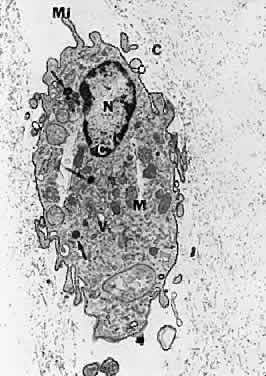

There are cells embedded within the posterior vitreous cortex (Fig. 18) known as hyalocytes. Situated 20 to 50 μm from the ILL of the retina, these mononuclear cells are widely spread apart in a single layer (Fig. 19). The highest density of hyalocytes is in the region of the vitreous base, followed by the posterior pole, with the lowest density at the equator. Derived from circulating monocytes and renewed every 6 months, hyalocytes are oval or spindle-shaped and are 10 to 15 μm in diameter. They contain a lobulated nucleus, a well-developed Golgi complex, smooth and rough endoplasmic reticula, many large periodic acid-Schiff-positive lysosomal granules, and phagosomes (Fig. 20). Balazs72 noted that hyalocytes are located in the region of highest HA concentration and suggested that these cells may be responsible for vitreous HA synthesis, which may also be true of vitreous collagen.

Fig. 20. Ultrastructure of human hyalocyte. A mononuclear cell is seen embedded within the dense collagen fibril (black C) network of the vitreous cortex. There is a lobulated nucleus (N) with a dense marginal chromatin (white C). In the cytoplasm, there are mithochondria (M), dense granules (arrows), vacuoles (V), and microvilli (Mi). (×11,670.) (Courtesy of Joe Craft and Dan Albert, MD)

The phagocytic capacity of hyalocytes derives from the presence of pinocytic vesicles, phagosomes (Fig. 20), and cell membrane receptors that bind immunoglobulin G (IgG) and complement. It is intriguing to consider that hyalocytes are among the first cells to be exposed to any migratory or mitogenic stimuli released during various disease states. Because hyalocytes are essentially tissue macrophages, they may have a role similar to macrophages in other diseases, i.e., to recruit cells and elicit further escalation of the inflammatory response. Whereas in some tissues this may be desirable, in the vitreous this process results in various untoward events, depending on the clinical circumstances. In the case of pars planitis, hyalocytes in the vitreous base may be responsible for antigen processing and eliciting an immune response typical of tissue macrophages that leads to the observed snow banks of inflammatory cells in the peripheral anterior vitreous. Indeed, for these and other reasons, this condition may be more aptly named peripheral anterior vitritis. After failed surgery for rhegmatogenous RD, hyalocytes are likely the first cells to participate in the formation of the contractile membranes that in PVR detach the retina again. The particularly high density of hyalocytes in the vitreous base may be important in the pathogenesis of anterior PVR, wherein the prominence of vitreous fibers also contributes to the disease process by facilitating cell migration and transmitting traction to the peripheral retina, ciliary body, and iris. Thus, the role of these cells must be adequately considered in defining the pathophysiology of PVR, perhaps leading to a new avenue for early intervention.